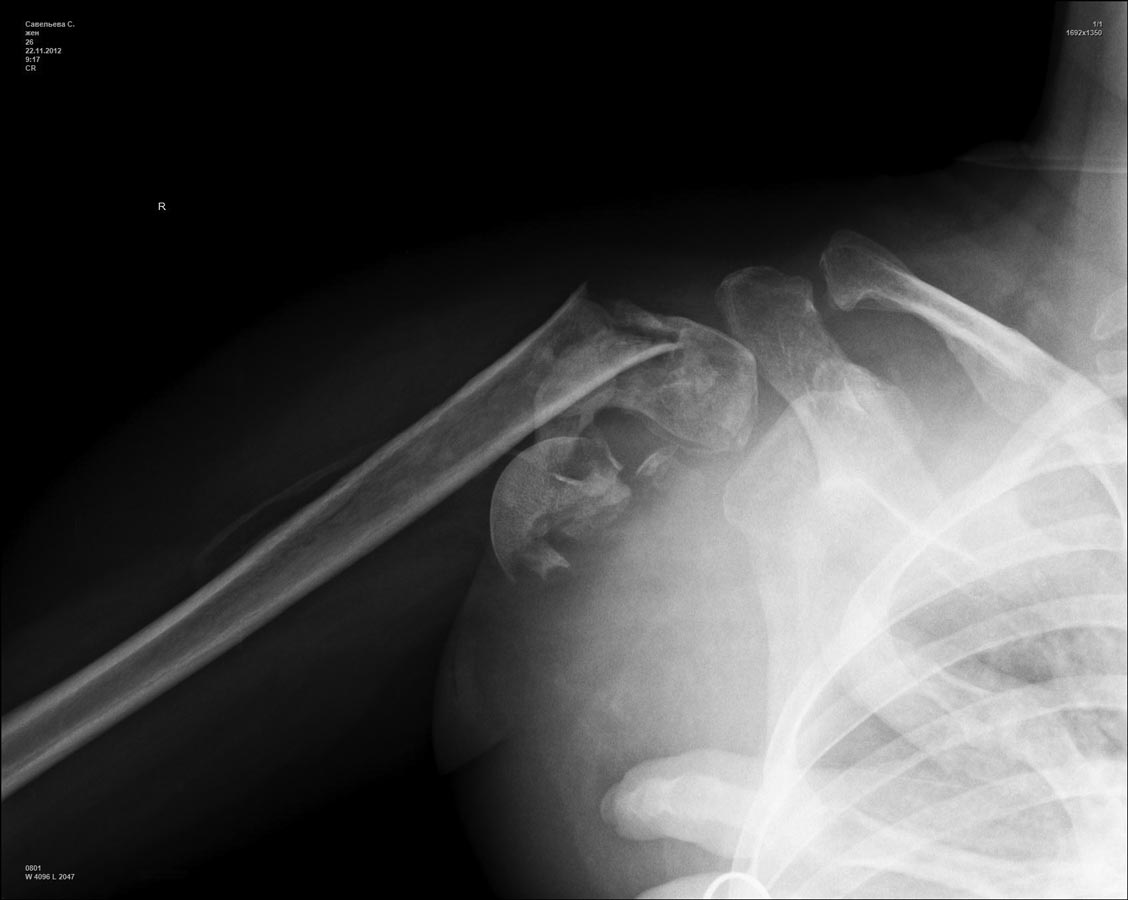

При переломах проксимального плеча, кроме обычных рентген снимков, необходимо сделать КТ исследование. Особенно 3D реконструкция, которая даст полную информацию о расположении фрагментов, потому что от количества фрагментов зависит тактика лечения. Переломы из 4х фрагментов приведет к остеонекрозу и поэтому прямое показание к эндопротезированию. Переломы с меньшим количеством фрагментов успешно могут быть синтезированы!

Из всех возможностей лечения протезирование было бы самым легким решением? и можно остановиться на hemiarthroplasty. Здесь костные фрагменты расположились разнонаправленно, и при решении на протезирование желательно сохранить большой бугорок.

1) This a chronic, 4-part anterior fracture dislocation. How do I know it is anterior, and not posterior, only with a plain AP X-ray ??

Because posterior dislocations do not behave this way, radiographically, believe me. Also, there MAY be an A-C TYPE V dislocation in this shoulder ... But. let's forget that, now ...

Well, the patient is a young female, 26 years, who, unfortunately, had this severe problem NOT properly diagnosed.